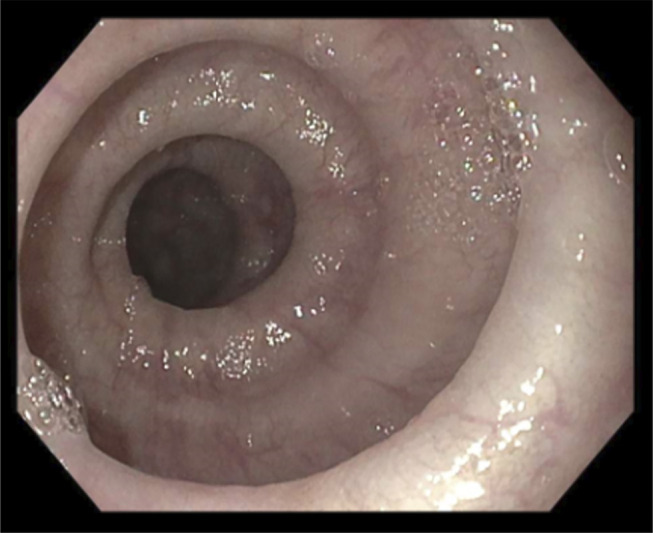

Where the Jackhammer Meets the Corkscrew: A Case of Manometric Hypercontractile Esophagus and Esophagogastric Junction Outflow Obstruction With Endoscopic Features of Distal Esophageal Spasm.